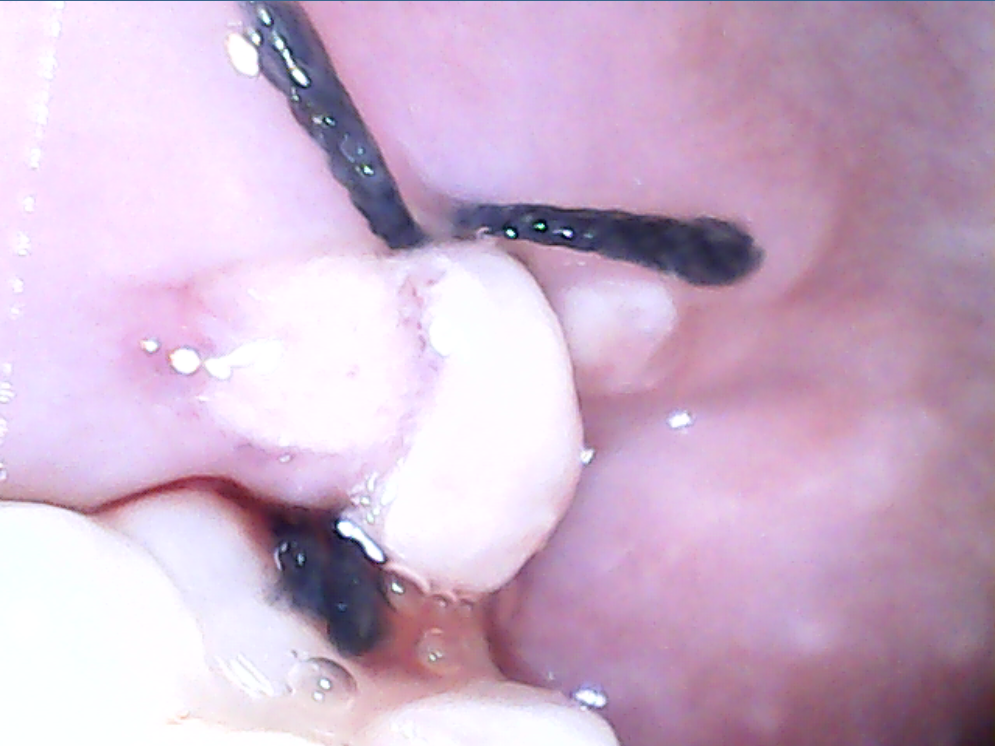

염증은 아니고 상처가 치유되면서 생기는것과 음식물 잔여물이 실밥에 껴서 그럴수도 잇습니다. 불편하시면 가까운 치과 아무데나 가셔서 소독한번 받으시면될것같습니다.